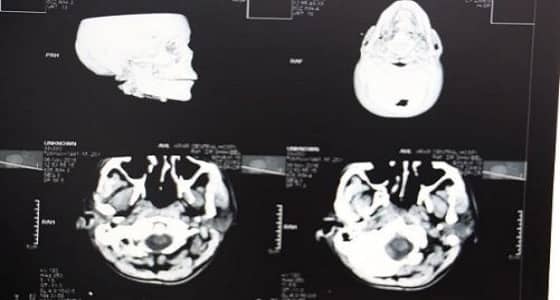

تمكّن فريق طبي بمستشفى عرعر المركزي من إنقاذ حياة مقيم إثر تعرضه لحالة دهس، حيث كان يعاني من إصابات متعددة انتفاخ واحتشاء نزفي شديد بالمخ ، كسر بالجمجمة والفك ، انحراف شديد للخط الناصف للمخ ، كسر بكامل القدم اليسرى.

وقام الفريق الطبي بقيادة استشاري جراحة المخ والأعصاب بإجراء عملية خزع جمجمة طارئ والاحتفاظ بجزء من عظم الجمجمة في جدار البطن، وذلك للسماح بتمدد أنسجة المخ خارج تجويف الجمجمة وتقليل الضغط داخل المخ حيث أثمرت نتائجها - بحمد الله -. وبعد استقرار حالة المريض تم إجراء العملية الثانية وهي تجميلية بالوجه للجهة المتضررة وبعد تحسن حالة المريض تم عمل العملية الجراحية الثالثة وإعادة تثبيت عظم الجمجمة في مكانه، وبعد أن تحسنت حالته الصحية تم السماح له بالخروج من المستشفى وهو بصحة جيدة ووضعه الصحي مستقر.